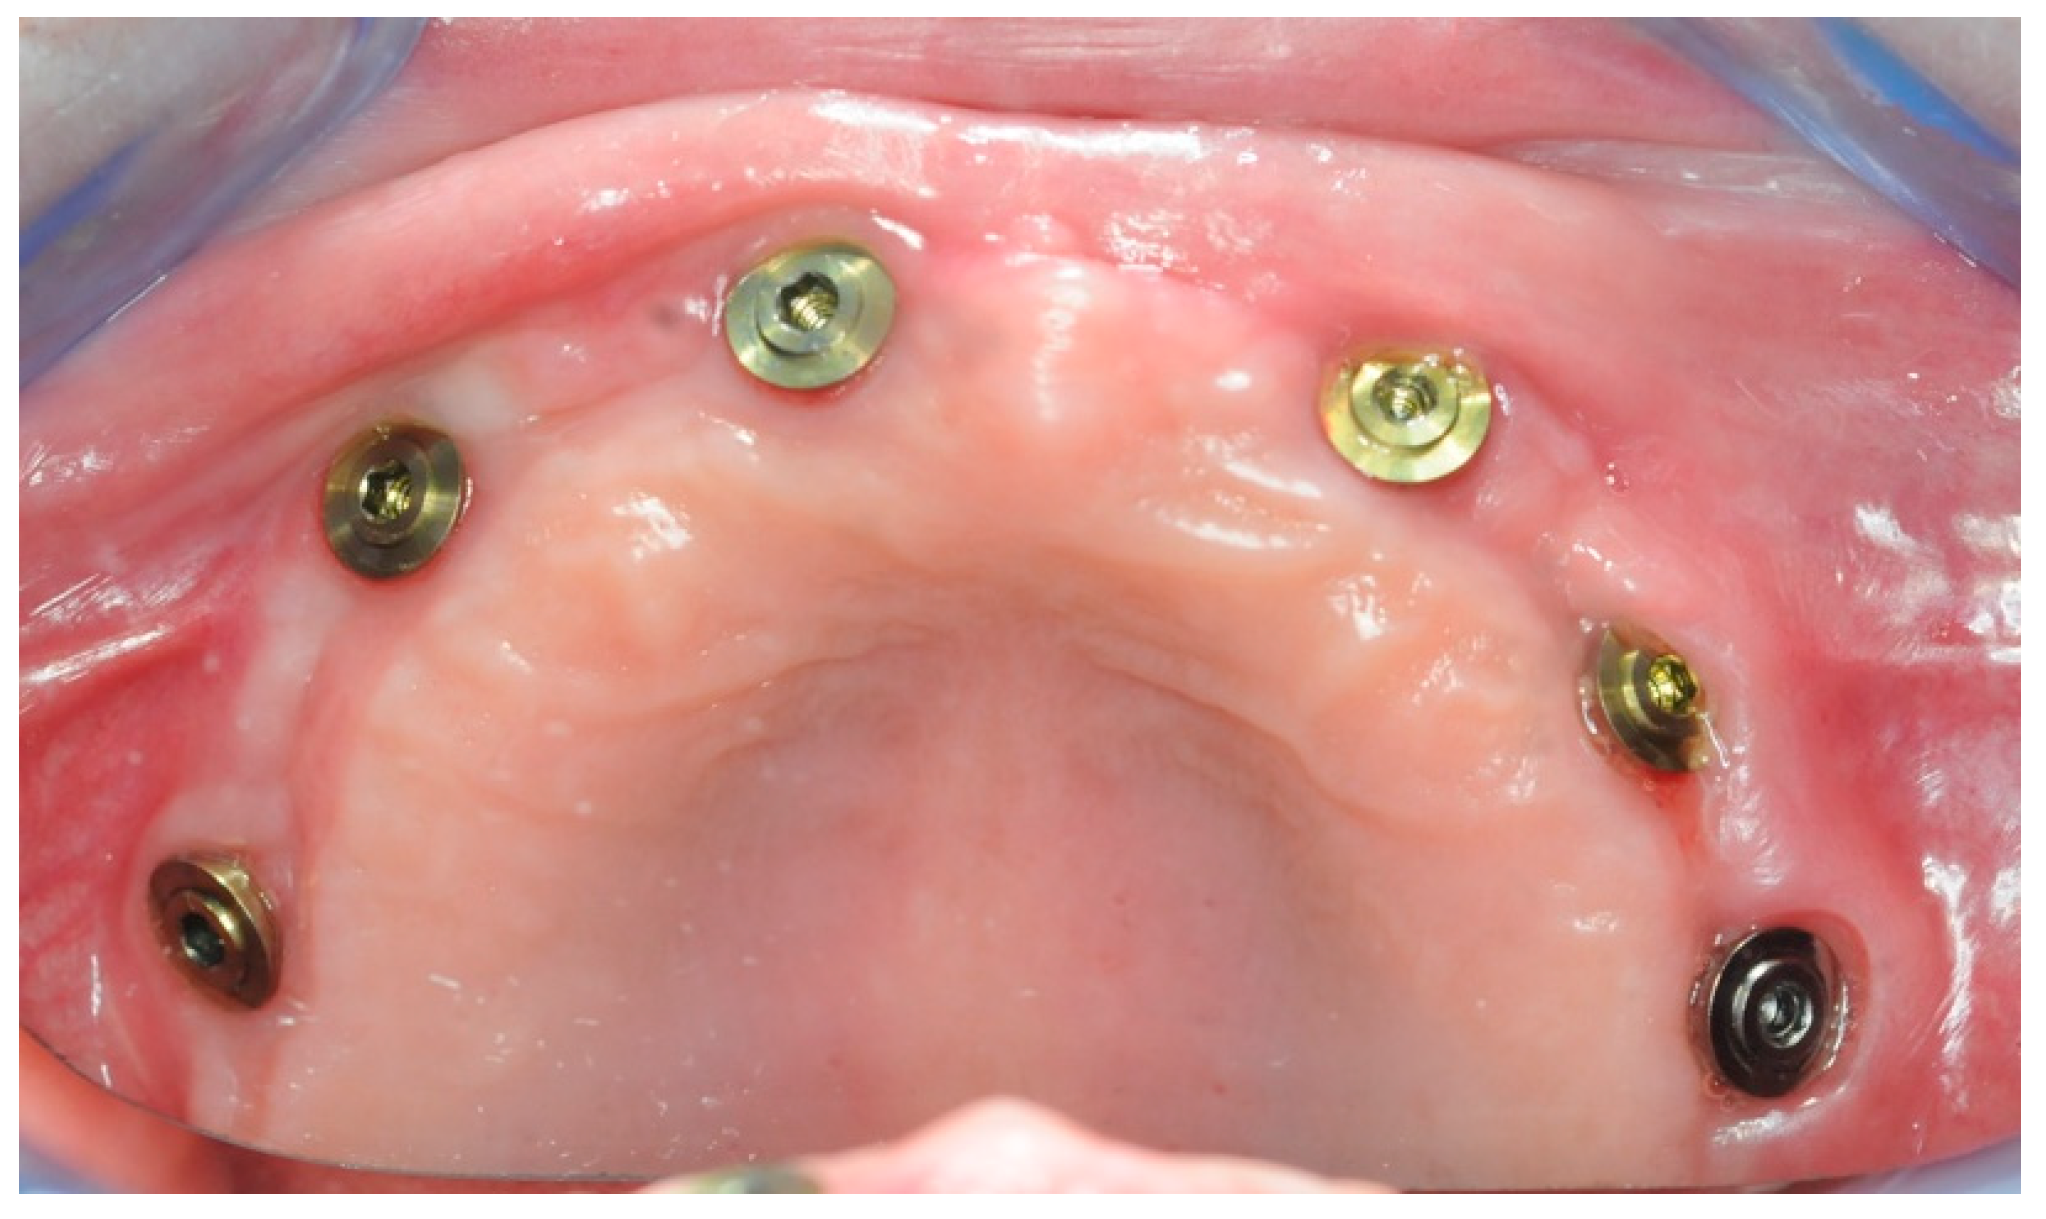

2.4. Temporary Prosthesis